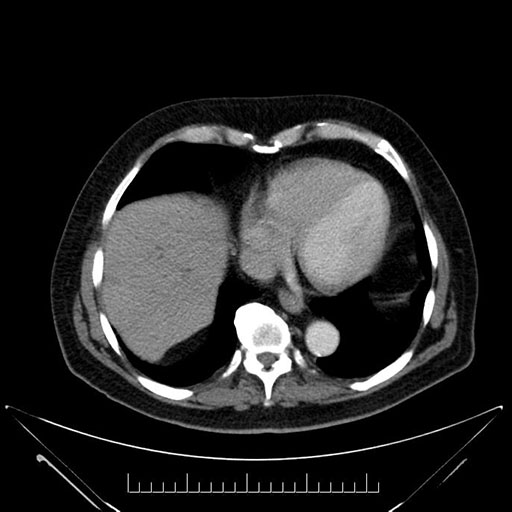

Imaging Analysis

Look through the patient's CT scan to identify any areas of concern for the necessary procedure.

Based on your CT findings, which issue(s) would give reason for "planned slowing down moment(s)" in this case?